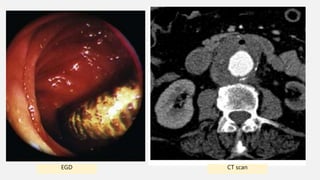

CT scan —> a preferred initial diagnostic test;

CT scans are less invasive than EGD or angiography,

are easy to obtain, and do not risk thrombus dislodgement.16

• CT scan : The detection rate of CT for AEF is the highest of all

modalities (61%)

• EGD : The detection rate of AEF by EGD is 25%

• Angiography : The angiography detection rate for AEF is 26%

CT scanEGD